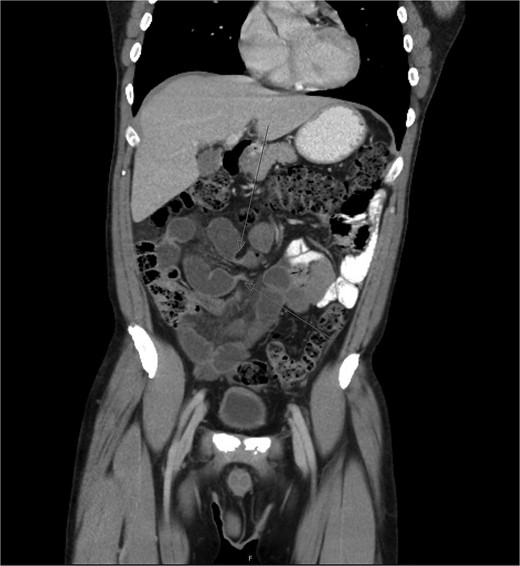

During diagnostic laparoscopy, a loop of jejunum was found to be transomentally herniated, congested but viable (Figs 2 and 3). Adhesiolysis was performed, and no small bowel resection was required. The patient was discharged on postoperative day 2 after an uneventful recovery and has not experienced any complications since.

Intraoperative image from diagnostic laparoscopy showing a loop of jejunum herniating through a defect in the greater omentum.